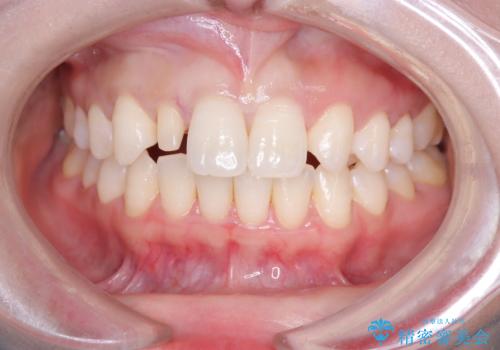

- 「前歯の見た目が気になる」を主訴に来院された患者様です。

右上2が矮小歯だったので、オールセラミッククラウンで審美修復しました。

見た目が改善され、大変ご満足いただけました。